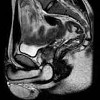

МРТ органов малого таза у мужчин

МРТ органов малого таза у человека. Неинвазивный и безопасный метод получения послойного изображения органов мочи у человека, основанный на свойствах протонов для радиочастотных импульсов в интенсивном магнитном поле. Во время МРТ оценивается структура предстательной железы, семенных пузырьков, семявыносящего протока, мочевого пузыря, прямой кишки, лимфатических узлов, сосудов и жировой ткани в полости таза. МРТ органов малого таза у человека является информативным для диагностики злокачественных опухолей ОМТ, доброкачественной гиперплазии предстательной железы, крипторхизма, мочевых камней, паравезикальных абсцессов, метастазов и Исследование проводится с умеренно заполненным мочевым пузырем, в процессе диагностики может потребоваться введение контрастного вещества.